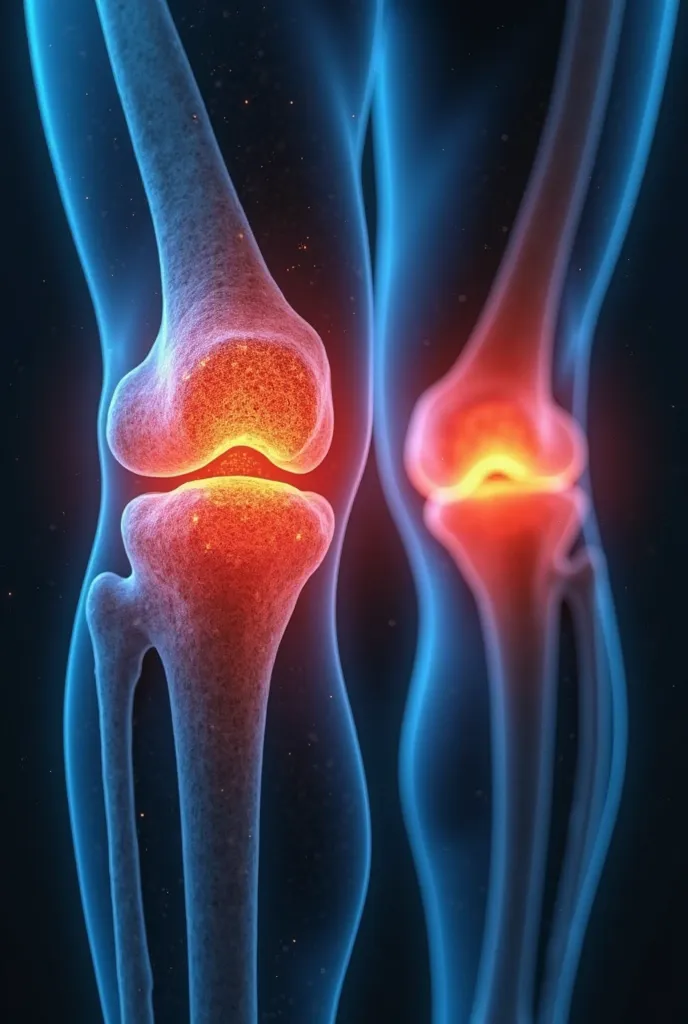

Create a realistic image depicting muscle pain in the leg. Show a person in a na

Create a realistic image depicting muscle pain in the leg. Show a person in a natural posture, with one hand placed on the area where you feel muscle pain. The area of pain should be highlighted with a reddish hue to indicate discomfort.. The person's expression should reflect mild distress or discomfort.. The image must have realistic skin textures and lighting., and the background should be neutral to focus attention on the person and the highlighted area of pain

Create a realistic image depicting muscle pain in the leg

Show a person in a natural posture

with one hand placed on the area where you feel muscle pain

The area of pain should be highlighted with a reddish hue to indicate discomfort

s expression should reflect mild distress or discomfort

The image must have realistic skin textures and lighting

and the background should be neutral to focus attention on the person and the highlighted area of pain